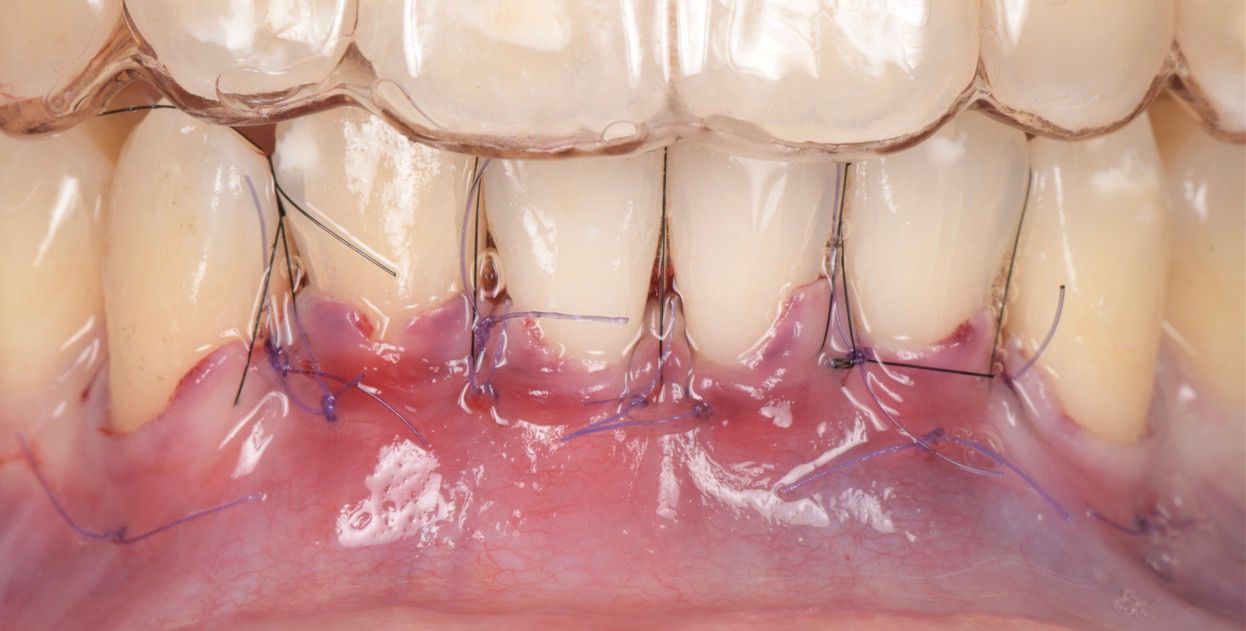

The first connective tissue graft was placed on denuded roots of #43, #42, and #41 (Fig. 6), and the second on #31, #32 and #33 (Fig. 7), which all had previously been treated with Straumann® Emdogain®.

The buccal flaps were coronally displaced and sutured with 6/0 sutures and tension-free closure (Fig. 8).